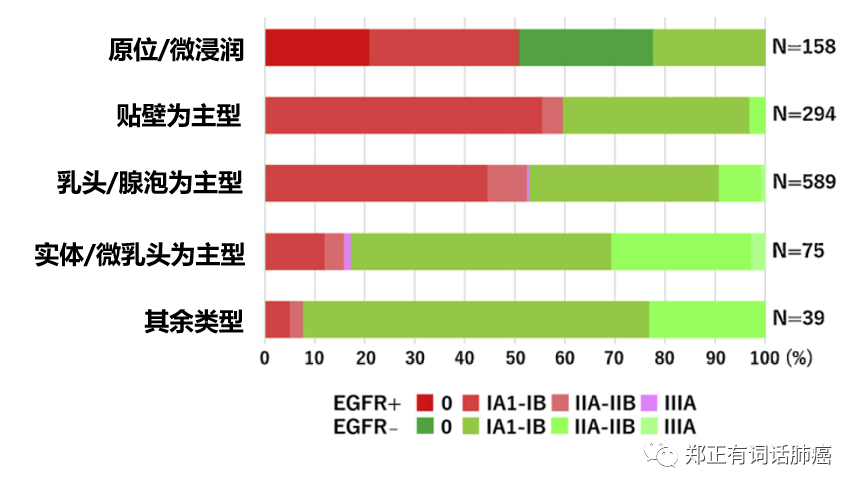

进一步分层分析显示:

原位腺癌/微浸润腺癌群体,EGFR突变比例50.9%;

贴壁为主腺癌群体,EGFR突变比例59.7%;

乳头/腺体泡为主腺癌群体,EGFR突变比例53.0%;

实体/微乳头为主腺癌群体,EGFR突变比例17.3%;

0-IB期群体,EGFR突变比例52.2%;

IIA-IIIA期群体,EGFR突变比例为40.7%。

可见,携带EGFR突变的肺腺癌更多是早期且恶性度较低的患者。